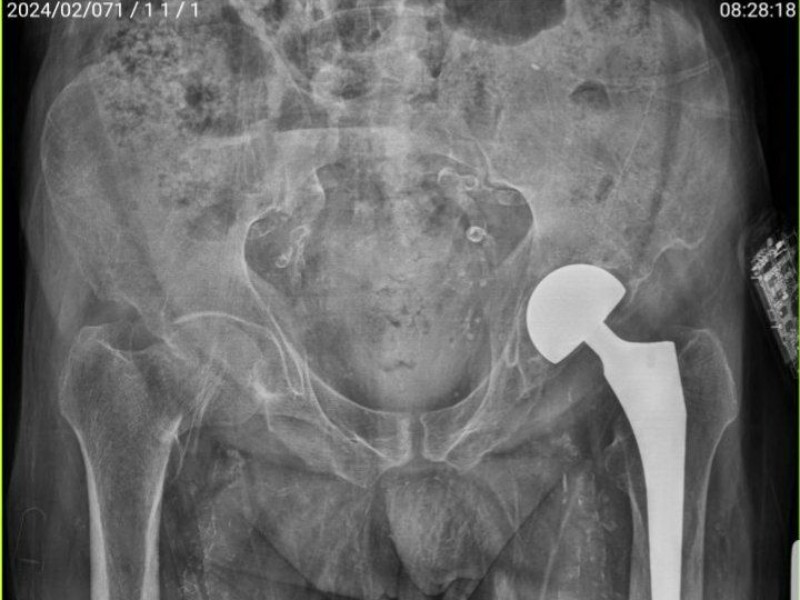

به گزارش هزارماسوله ، مدیر بیمارستان پاوه با اعلام این خبر به خبرنگار ما گفت: آقای ۷۲ ساله با سابقه دیابت نوع ۲ ، نارسایی کلیه و انجام دیالیز و نارسایی قلبی به دنبال سقوط دچار شکستگی و در رفتگی لگن راست شدند و توسط مرکز فوریت های پزشکی به بیمارستان ارجاع داده می شود.

خانم دکتر طاهره رشیدی افزود: پس از پذیرش و هماهنگی با متخصص ارتوپدی بیمارستان ، پرسنل اتاق عمل و تیم بیهوشی با توجه به شرایط بیمار و عدم پذیرش از مراکز درمانی به جهت ریسک بیهوشی و عمل ، با رضایت خانواده مصدوم، دکتر سخایی متخصص ارتوپدی اقدام به انجام عمل و تعویض مفصل بیمار نمود و بیمار پس از ریکاوری با حال مساعد به بخش منتقل می شود.